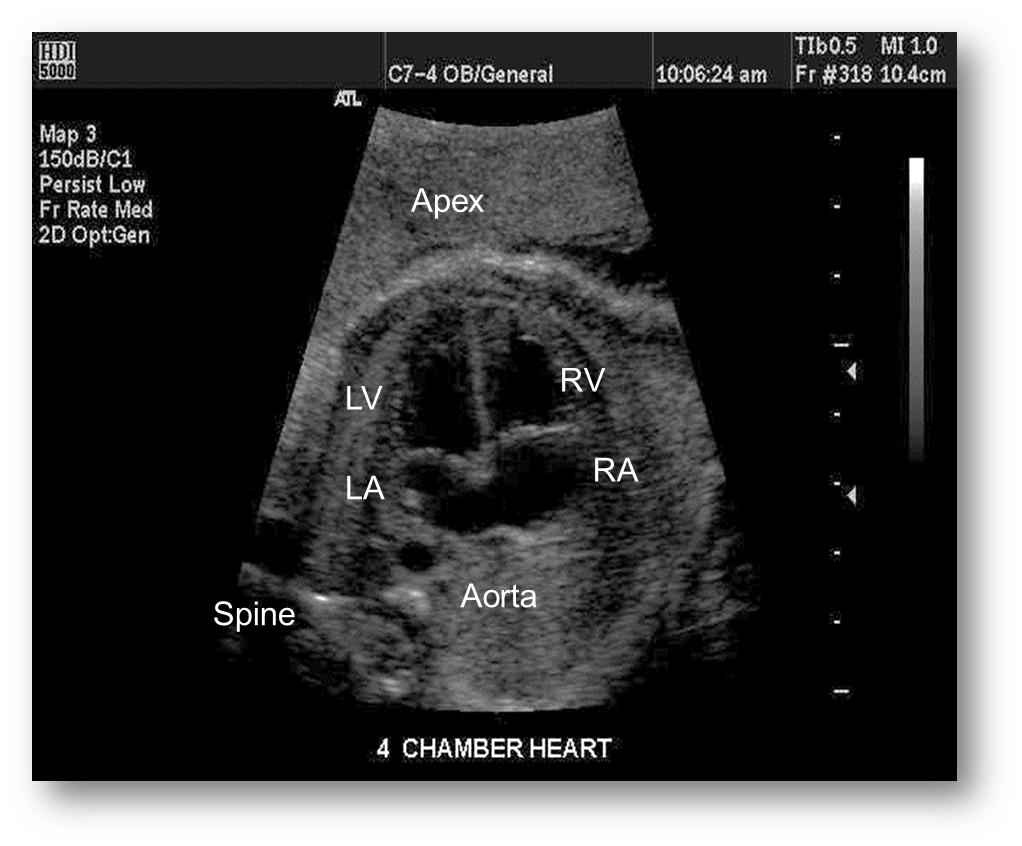

What view is this?

4 chamber view

Normal 4 chamber view

Identify structures of the heart